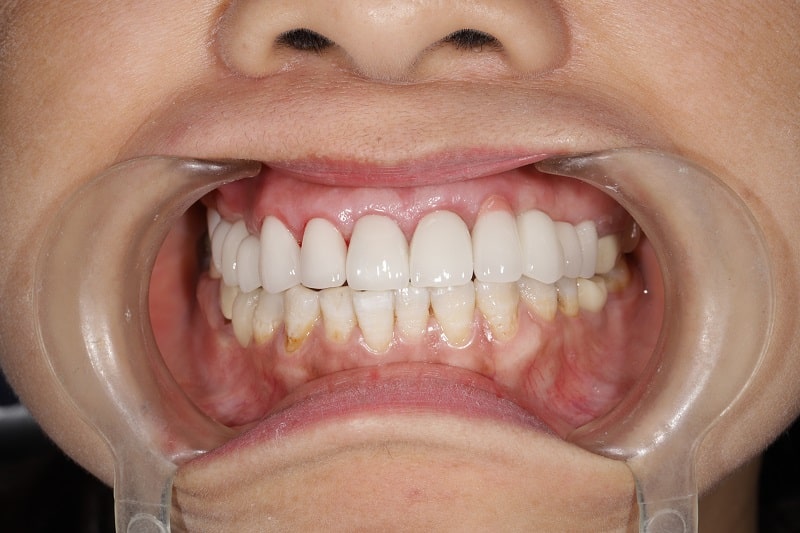

2.3 Trám răng nhựa Composite

2.3.5 -Ưu điểm:

Composite là vật liệu trám được sử dụng phổ biến hiện nay bởi tính thẩm mỹ đạt hiệu quả tối đa, tương thích màu giống với răng thật. Vật liệu được chọn để sử dụng trám răng cửa và có tính linh hoạt sử dụng như: trám răng sứt mẻ, gãy mòn, răng ngắn, thưa,..

2.3.6 -Nhược điểm:

Chịu được lực ăn nhai kém nên dễ bị sứt mẻ và ăn mòn, theo đó tuổi thọ của vật liệu Composite ngắn, chỉ đạt khoảng 5 năm. Không được ưu tiên sử dụng trong trám răng hàm và chi phí vật liệu cao hơn so với hỗn hợp bạc Amalgam.